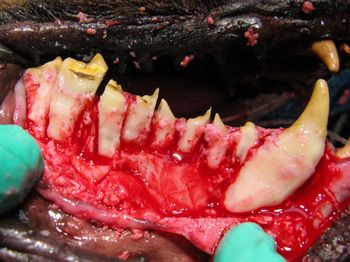

This veterinary dental condition, also called kissing lesions, can be extremely painful in affected pets and requires immediate and dedicated care.